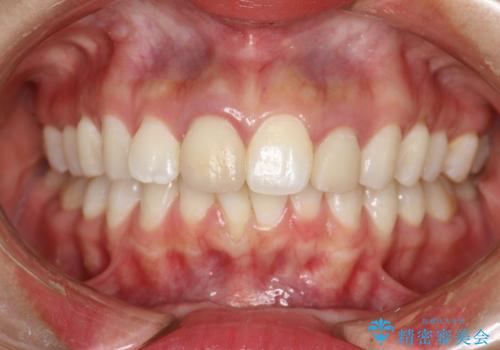

[ 矯正と補綴、総合歯科治療 ] クロスバイトを避ける前歯部審美ブリッジ

![[ 矯正と補綴、総合歯科治療 ] クロスバイトを避ける前歯部審美ブリッジの症例 治療後](https://seimitsushinbi.jp/wp/wp-content/uploads/2021/07/fcd77503a97e2f3a648f6e8698e34626-500x350.jpg?v=1626697051)